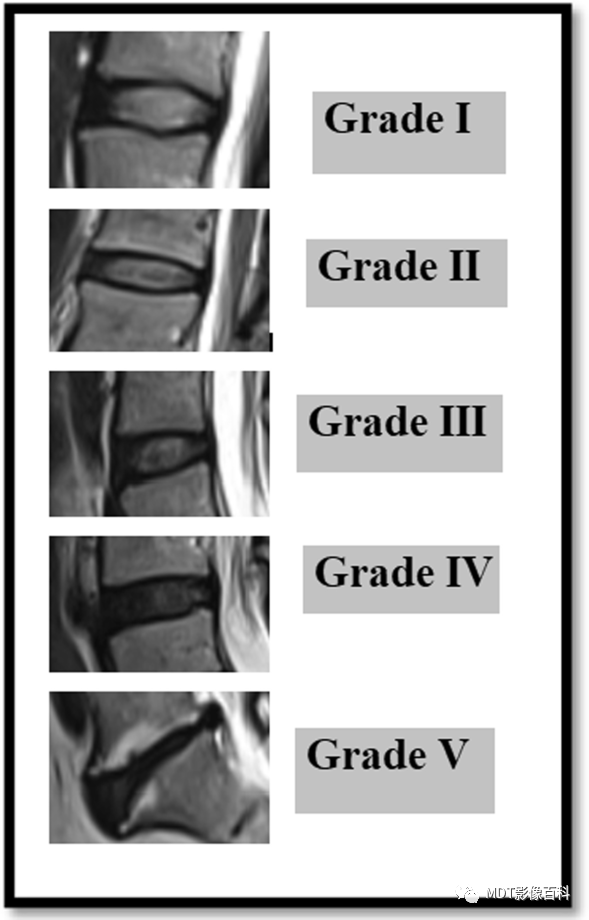

椎间盘退变的Pfirrmann分级系统

Pfirrmann分级系统是利用MRI对腰椎间盘退变进行分级的可靠分类系统。根据椎间盘信号强度、椎间盘结构、核与环之间的区别以及椎间盘高度,将退行性变分为5个等级。